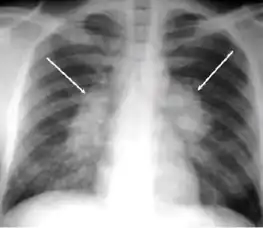

5. Hilar or mediastinal lymphadenopathy (bihilar lymphadenopathy) - Enlargement of lymph nodes in one or both hila or within the mediastinum, with or without associated atelectasis or consolidation.

Chest x-ray showing bilateral hilar adenopathy of primary pulmonary TB